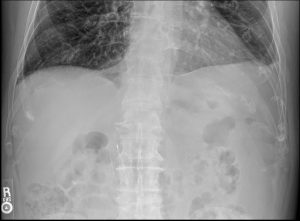

Radiographic analysis identified an incidental inferior vena cava (IVC) filter, an important finding due to its metallic structure that may mimic calcified densities, clips, or vascular changes on plain films. Recognition of this incidental IVC filter prevents misinterpretation, ensuring accurate distinction between foreign devices and potential pathology such as a renal calculus.

Using KUB X-ray and diagnostic ultrasound, the DACBR confirmed a radio-opaque calculus adjacent to the right L3 transverse process level—consistent with ureteral positioning. The incidental IVC filter, appearing as a metallic, linear structure near the midline, was duly noted. Its presence reinforced the necessity of careful pattern recognition and contextual imaging review.

In this case, the right ureteral stone was visible near L3, while the IVC filter projected midline across L2–L3—appearing as metallic filaments consistent with vascular intervention.

In this patient, ultrasound revealed a 5 mm hyperechoic shadowing focus in the proximal right ureter and mild hydronephrosis, confirming obstruction. The IVC filter was visible as bright linear echoes within the vena cava, confirming incidental yet benign status.